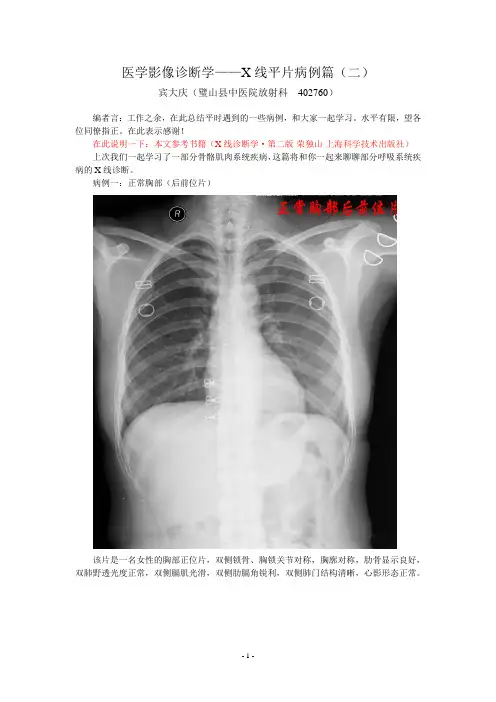

病例一:正常胸部(后前位片)该片是一名女性的胸部正位片,双侧锁骨、胸锁关节对称,胸廓对称,肋骨显示良好,双肺野透光度正常,双侧膈肌光滑,双侧肋膈角锐利,双侧肺门结构清晰,心影形态正常。